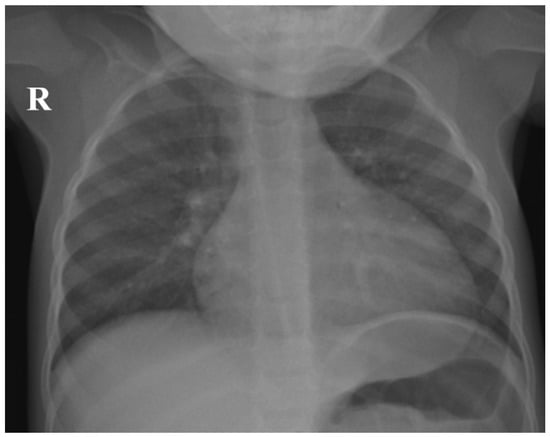

2. Case Report